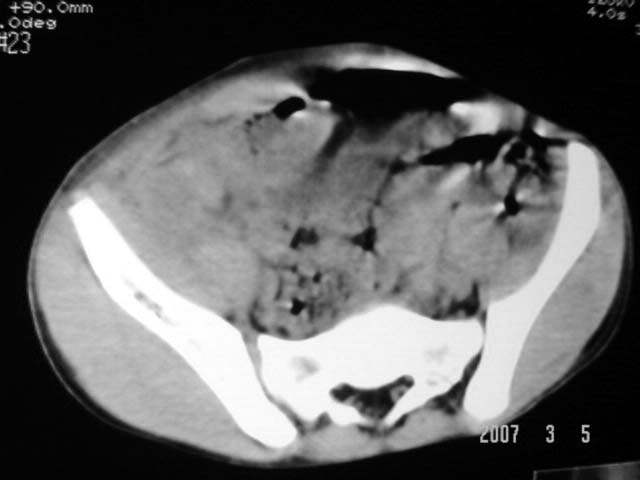

以下是引用dyqct在2007-3-5 10:28:00的发言:[br]右髂窝肿块。[br][br][br][br]